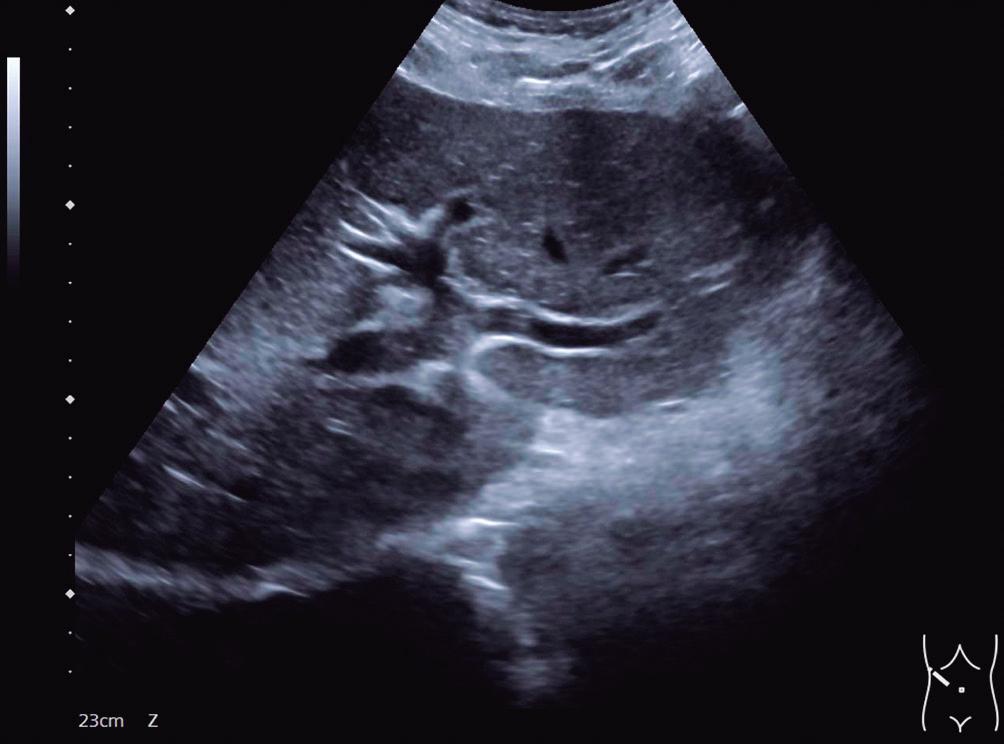

Presentación del caso

IC: intervalo de confianza; ITR: infección del tracto respiratorio; DS: desviacion standard; OR: odds ratio.

Grados de evidencia del grupo de trabajo GRADE.

Certeza alta: estamos muy seguros de que el efecto verdadero se aproxima al de la estimación del efecto.

Certeza moderada: tenemos una confianza moderada en la estimación del efecto; es probable que el verdadero efecto esté cerca de la estimación del efecto, pero existe la posibilidad de que sea sustancialmente diferente.

Certeza baja: nuestra confianza en la estimación del efecto es limitada; el verdadero efecto puede ser sustancialmente diferente de la estimación del efecto.